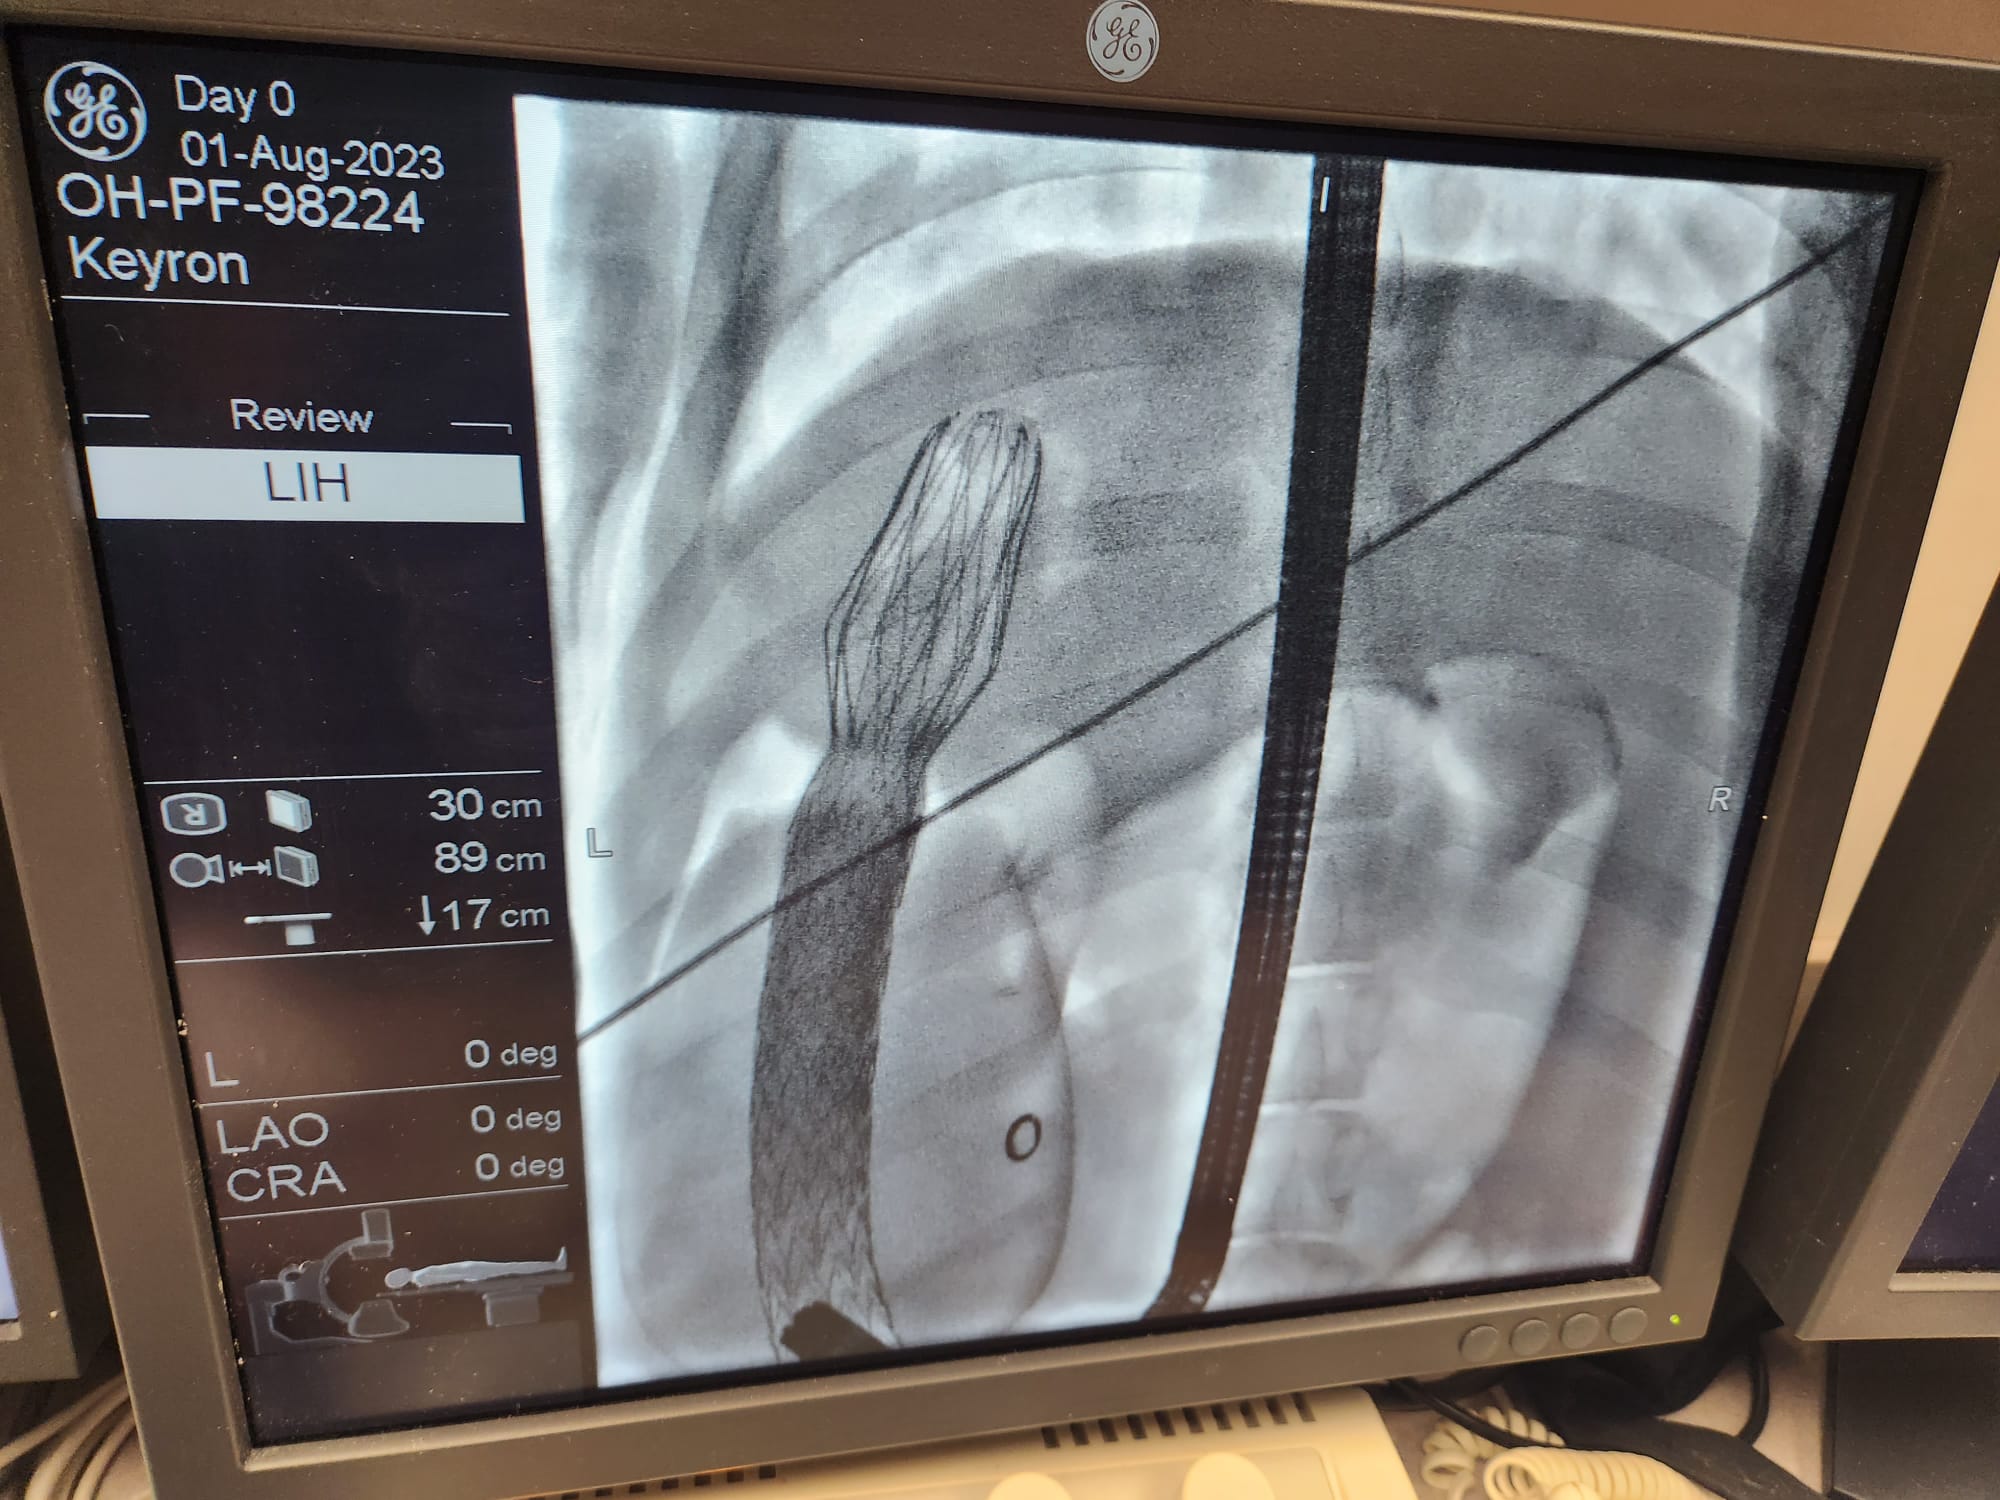

Our large animal data was published in Gut, the world’s leading journal in gastroenterology and hepatology, and the official journal of the British Society of Gastroenterology, with an exceptionally high impact factor of 25.8.

Pre-clinical studies have shown that the efficacy of ForePass ® may be unprecedented, and likely even better than Roux-en-Y Gastric Bypass surgery. Our long-term animal data shows (Δ from Baseline vs endoscopic controls):

Conclusion: ForePass ® reduced body weight, glycemia and insulin resistance, and liver fat deposition to the same level of gastric bypass surgery

We demonstrated a full reversal of diabetes and NASH, and weight loss, to levels not statistically different from gastric bypass surgery

ForePass ® is an extremely promising technology which may allow us to deliver the same benefits of metabolic surgery but without the complications from a surgical procedure